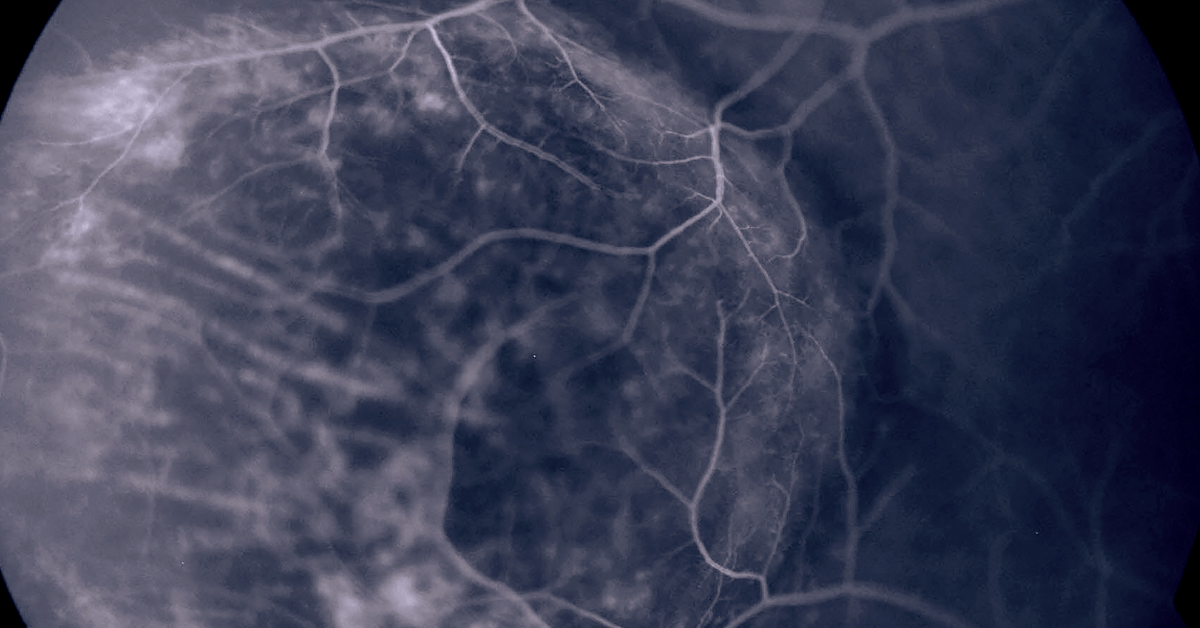

Central Serous Chorioretinopathy (CSCR) is when fluids from the choroid, a layer of tissues under the Retina, swell, creating a blister that can result in a small retinal detachment and visual distortion. Men in their 30s to 50s are more likely to develop CSCR than women, and those under a lot of stress are at particularly higher risk. Although long-term fluid accumulation can lead to permanent vision loss, if detected early, CSCR can be treated so that leaks are sealed and vision is restored. About half of the patients who have suffered from CSCR will have it return, so if you’ve ever experienced CSCR it’s critical to schedule regular follow-up exams with your Retinologist at High Country Macula. Learn more about CSCR at http://bit.ly/2Q5DTbH, and share with others who may be at risk.